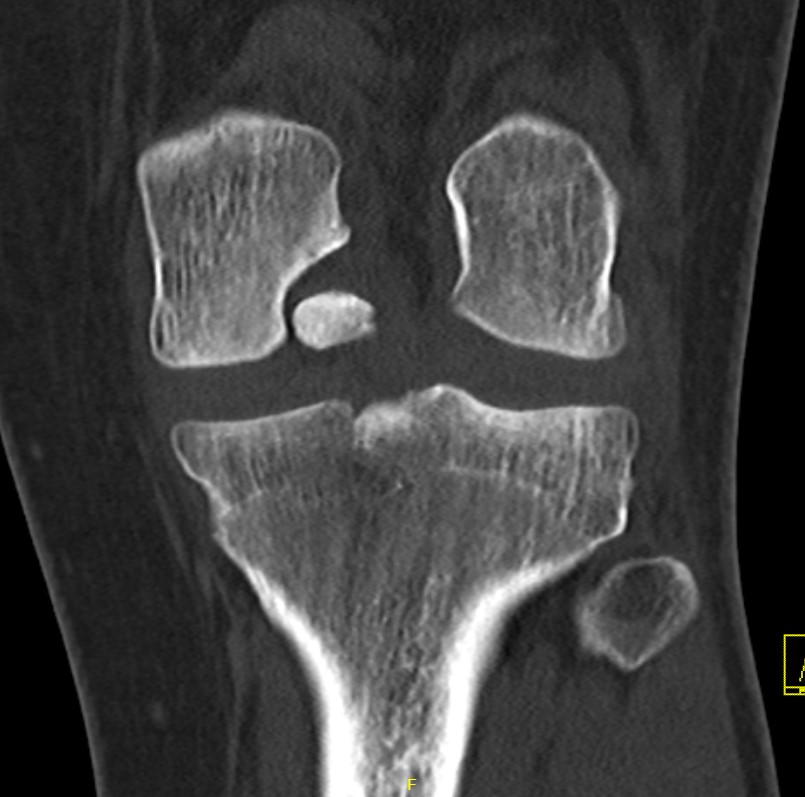

Stable lesion with no cysts Stable lesion with cysts

Assessing Union

Xray

Some reossification and evidence of union

MRI

Reossification and evidence of bony bridging

CT

Evidence of bony union on CT